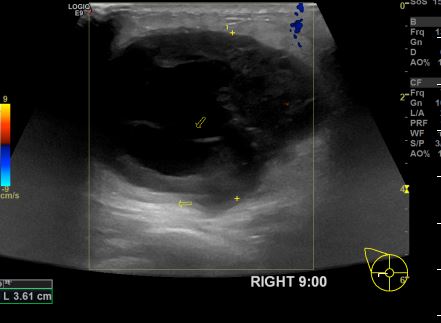

아산유외과개원후 655번째 유방암진단

상기환자 외부검사상 이상소견으로 내원하신 30대여성으로 우측에 의심스러운혹 조직검사시행해 유방암 진단되었습니다.